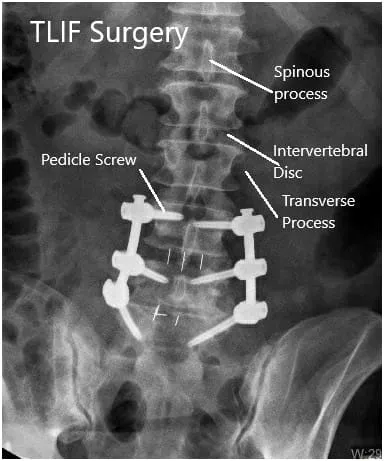

Intraoperative Fluoroscopic Images.

Postoperative X-ray in AP and Lateral views.